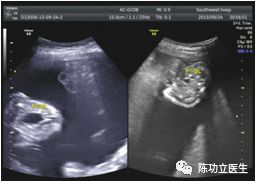

上图来源于西南医院超声科薛雅芳医生

TTTS分级(QUINTERO)

1期:供血儿最大羊水池<20mm,受血儿最大羊水池>80mm,20周后>100mm,供血儿膀胱可见;

2期:观察60min,供血儿膀胱不可见;

3期:任意胎儿出现多普勒异常;

4期:受血儿出现水肿、胸腔积液或腹腔积液等;

5期:胎儿死亡。